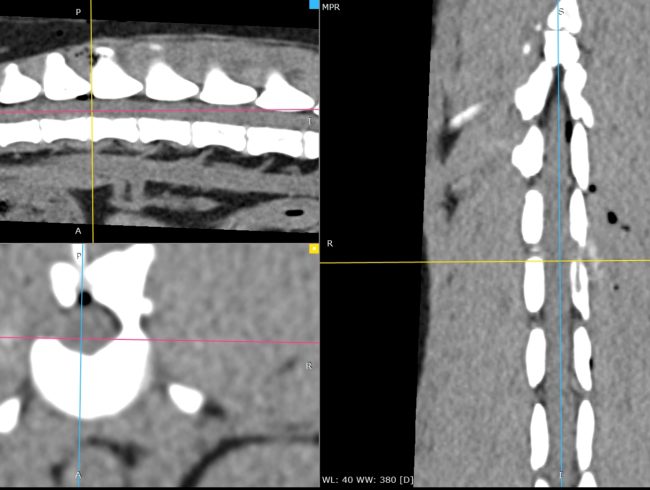

Hernie thoracolombaire sur un Teckel.

À gauche, reconstruction scanner multiplanaire mettant en évidence une hernie discale T13–L1 latéralisée à gauche, responsable d’une compression focale de la moelle épinière.